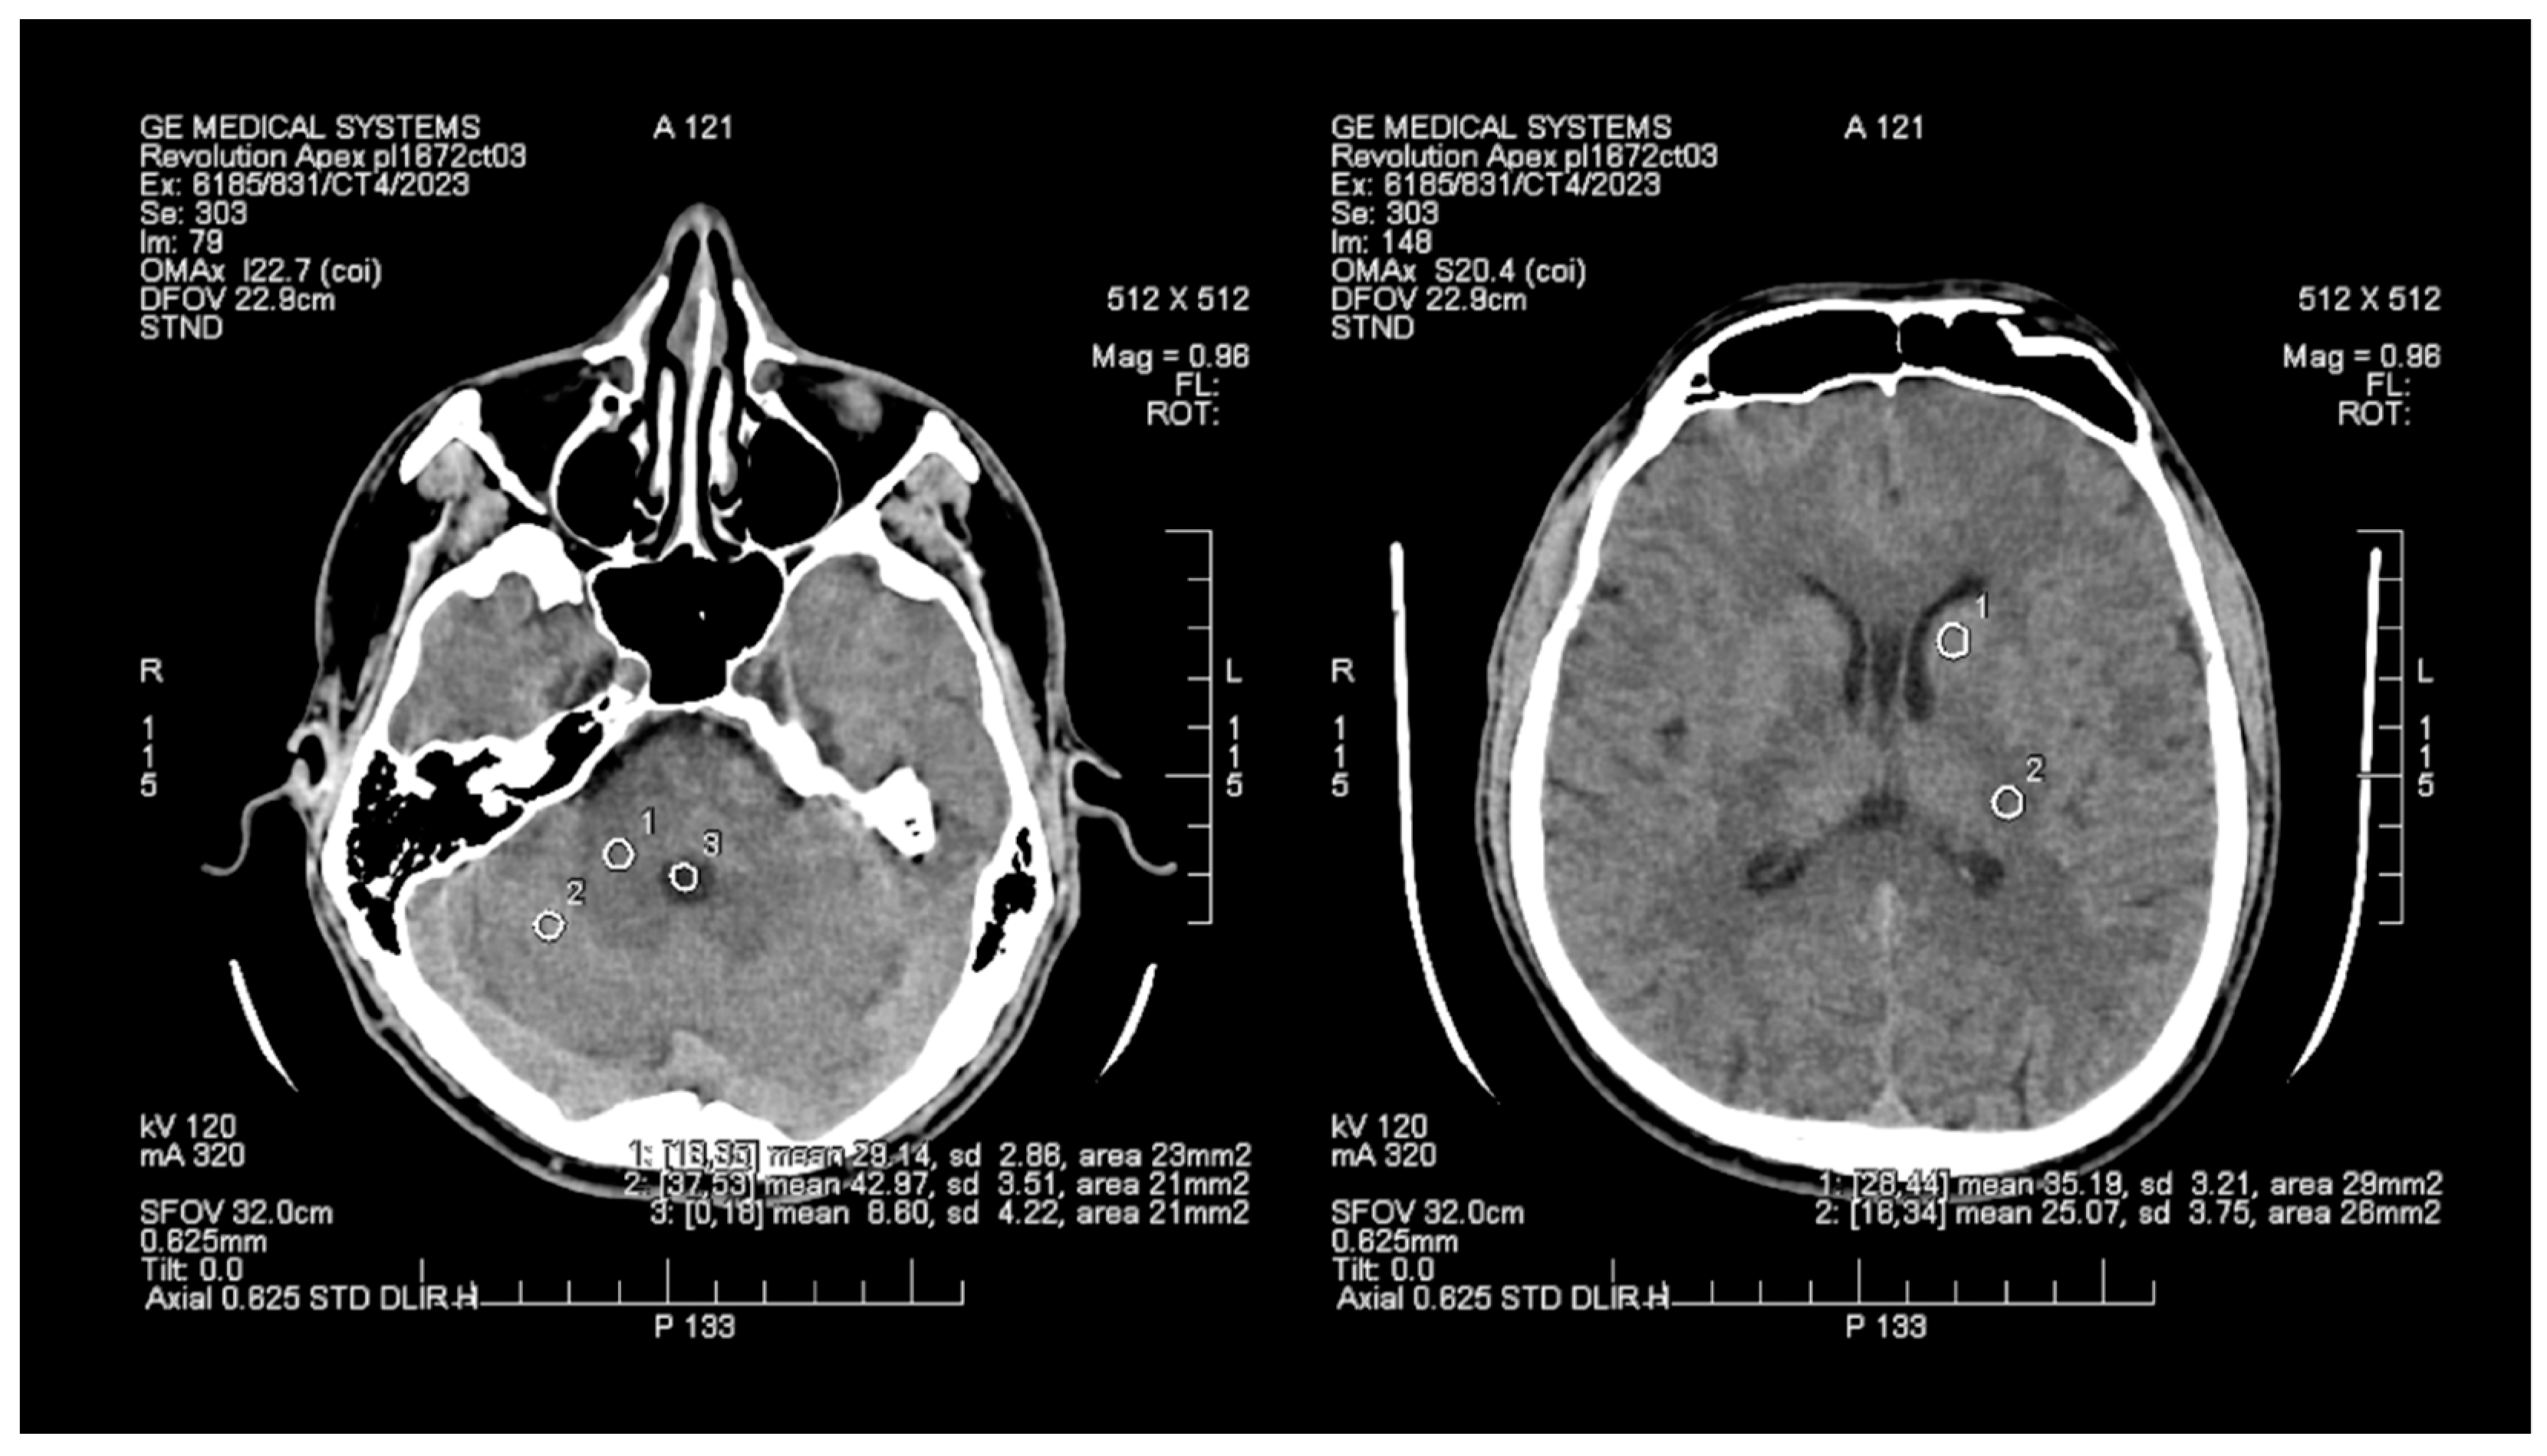

The objective assessment of image quality involved analyzing the signal-to-noise (SNR) and contrast-to-noise (CNR) ratios. To maintain consistency, a control variable was introduced in the form of manually set Regions of Interest (ROIs), which are analogous and predefined study areas in each pair of images. The average size of the ROI area was 24 mm2, with the smallest and the largest areas measuring 20 mm2 and 29 mm2, respectively. ROIs were positioned manually on the ASIR-V (Figure 1) reconstruction image, and then, duplicated at identical coordinates on the DLIR (Figure 2) reconstruction, which excluded potential deviations resulting from the lack of homogeneity of the measured tissues. The designation of the slice subject to the assessment was based solely on the anatomical factors of the patient. The first two ROIs were located in the white matter of the posterior limb of the internal capsule and the grey matter of the caudate nucleus, while the other two ROIs were positioned in the white and grey matter of the cerebellum. The fifth ROI was set in the cerebrospinal fluid of the fourth ventricle. To determine the signal level and noise, the mean CT number (mean) within the ROI and the standard deviation (SD) were taken into account.

Figure 2. Images of head CT with marked ROIs located in BGA (basal ganglia area) and PCF (posterior cranial fossa) obtained using DLIR.